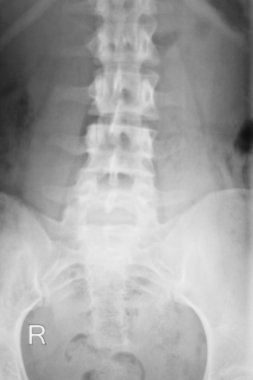

Sırt ve kereste omurgasının röntgen ışınları spondilotik değişimleri, sırt ve kereste dikenlerinin düzleştirilmesini, omurgalar arası disk alanlarının bozulmamış olduğunu, sırt ve kereste dikenlerinin Spondylosis 'inin bozulmamış olduğunu gösterir.